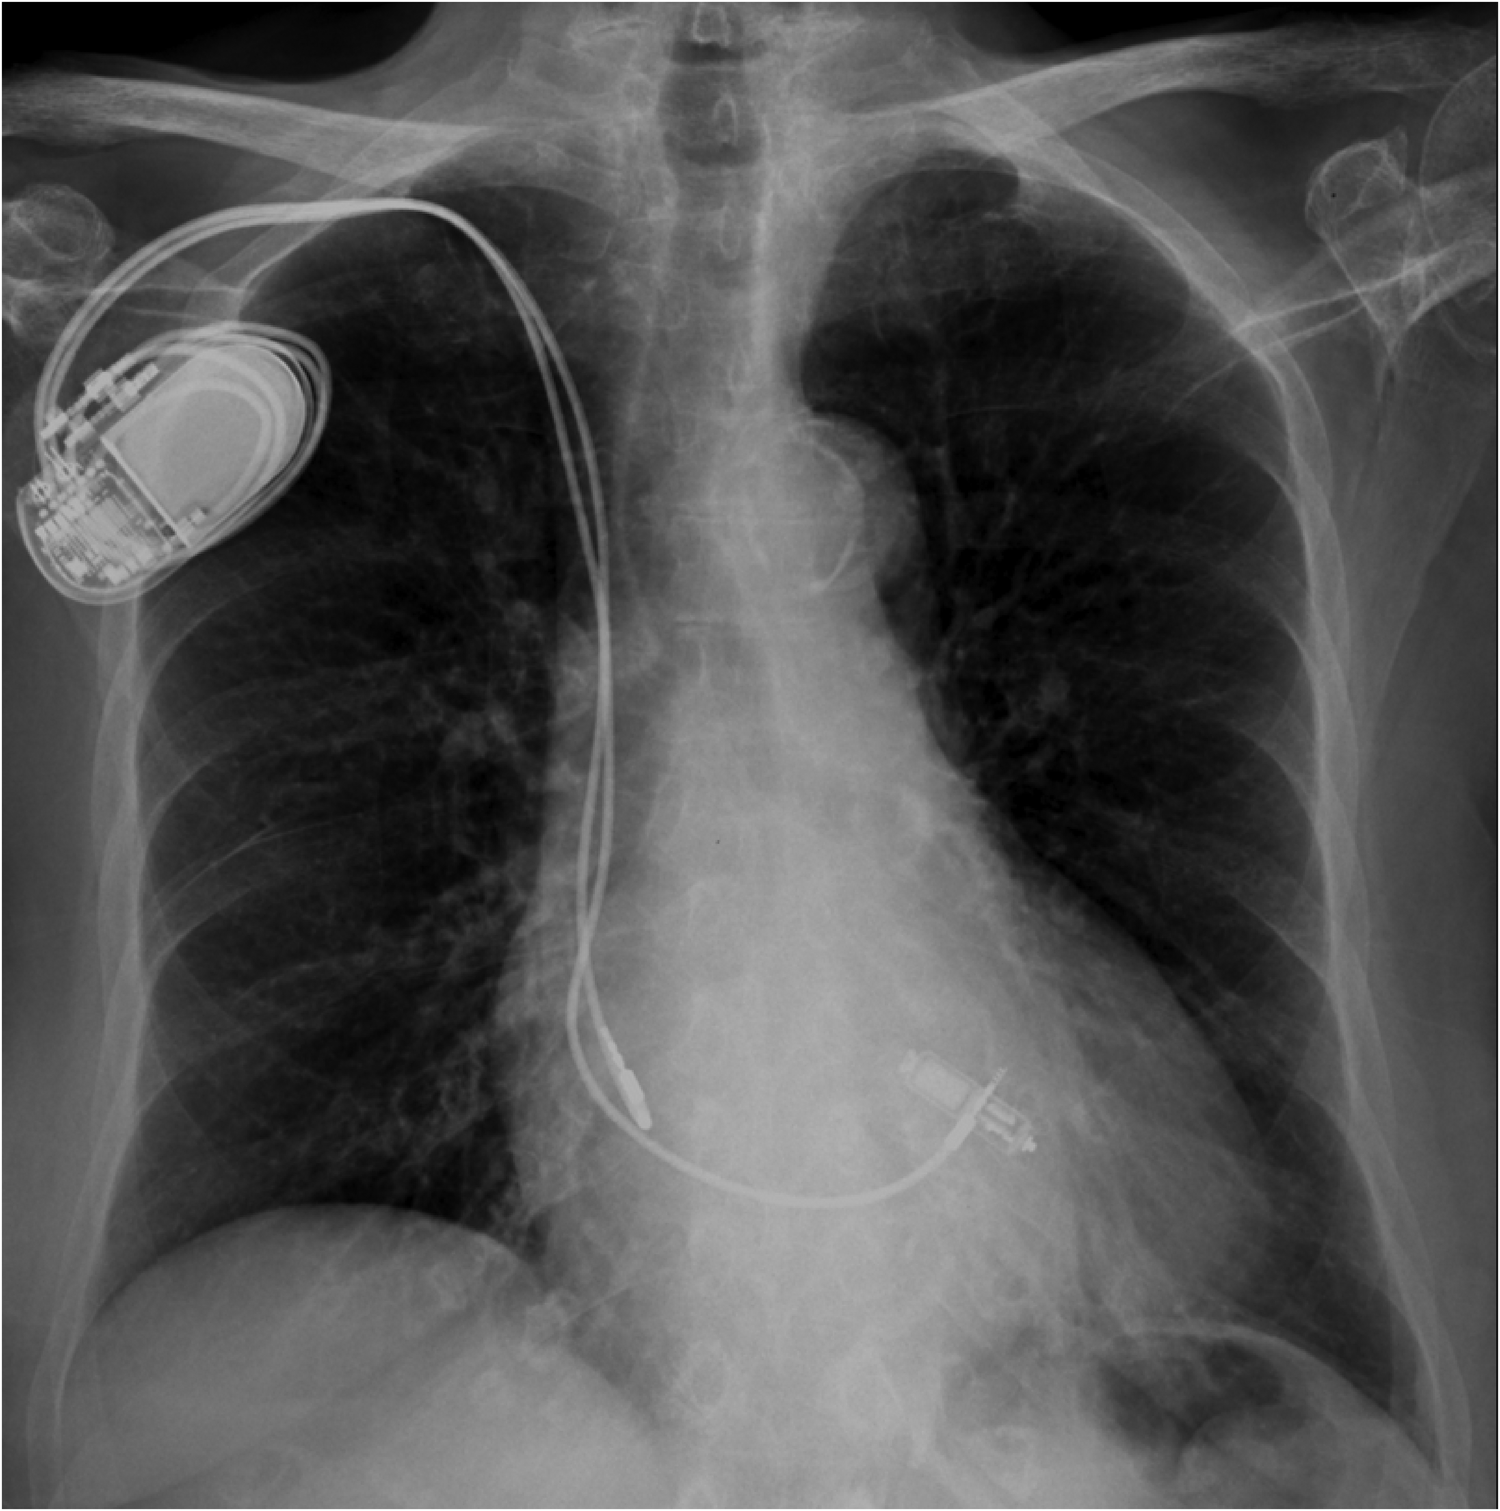

Figure 4

Post-procedural chest x-Ray showing a dual chamber transvenous pacemaker and a MICRA™ AV leadless pacemaker implanted at the interventricular septum.